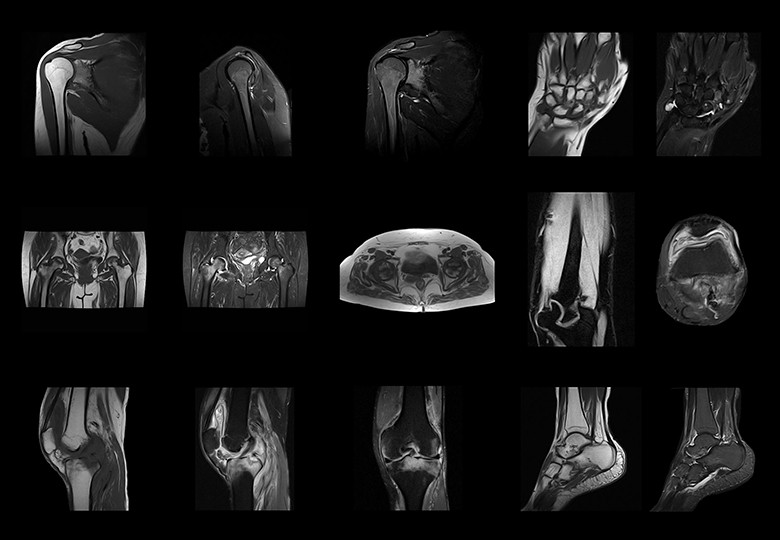

Album d'images cliniques

• Jointure